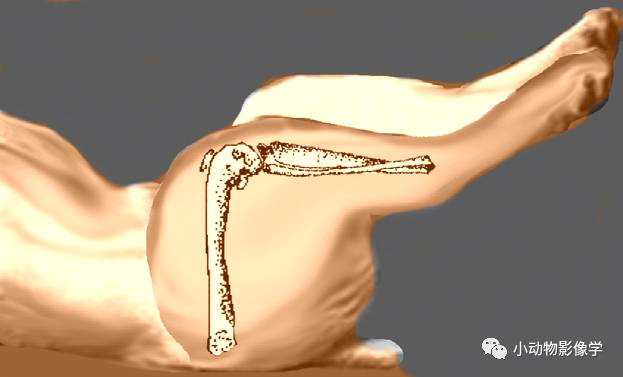

③髋关节伸展VD照

A.动物仰卧,后肢伸展并与骨盆平行

B.需要稍稍向内用力,人的手抓住两侧跗部。大型犬可以用胶带或绳子将膝关节处捆住。

⑤PennHIP

拍摄方法:通过压迫髋关节,拍摄X光判断髋关节是否松弛。拍摄时动物的股骨与骨盆垂直,并且在两股骨之间放入一个透射线的材料制成的牵引物,拍摄时稍微用力将两股骨远端往中间压迫。(腹背位)

此方法用于测量牵引指数,详细内容请参考《小动物放射诊断学》第7章